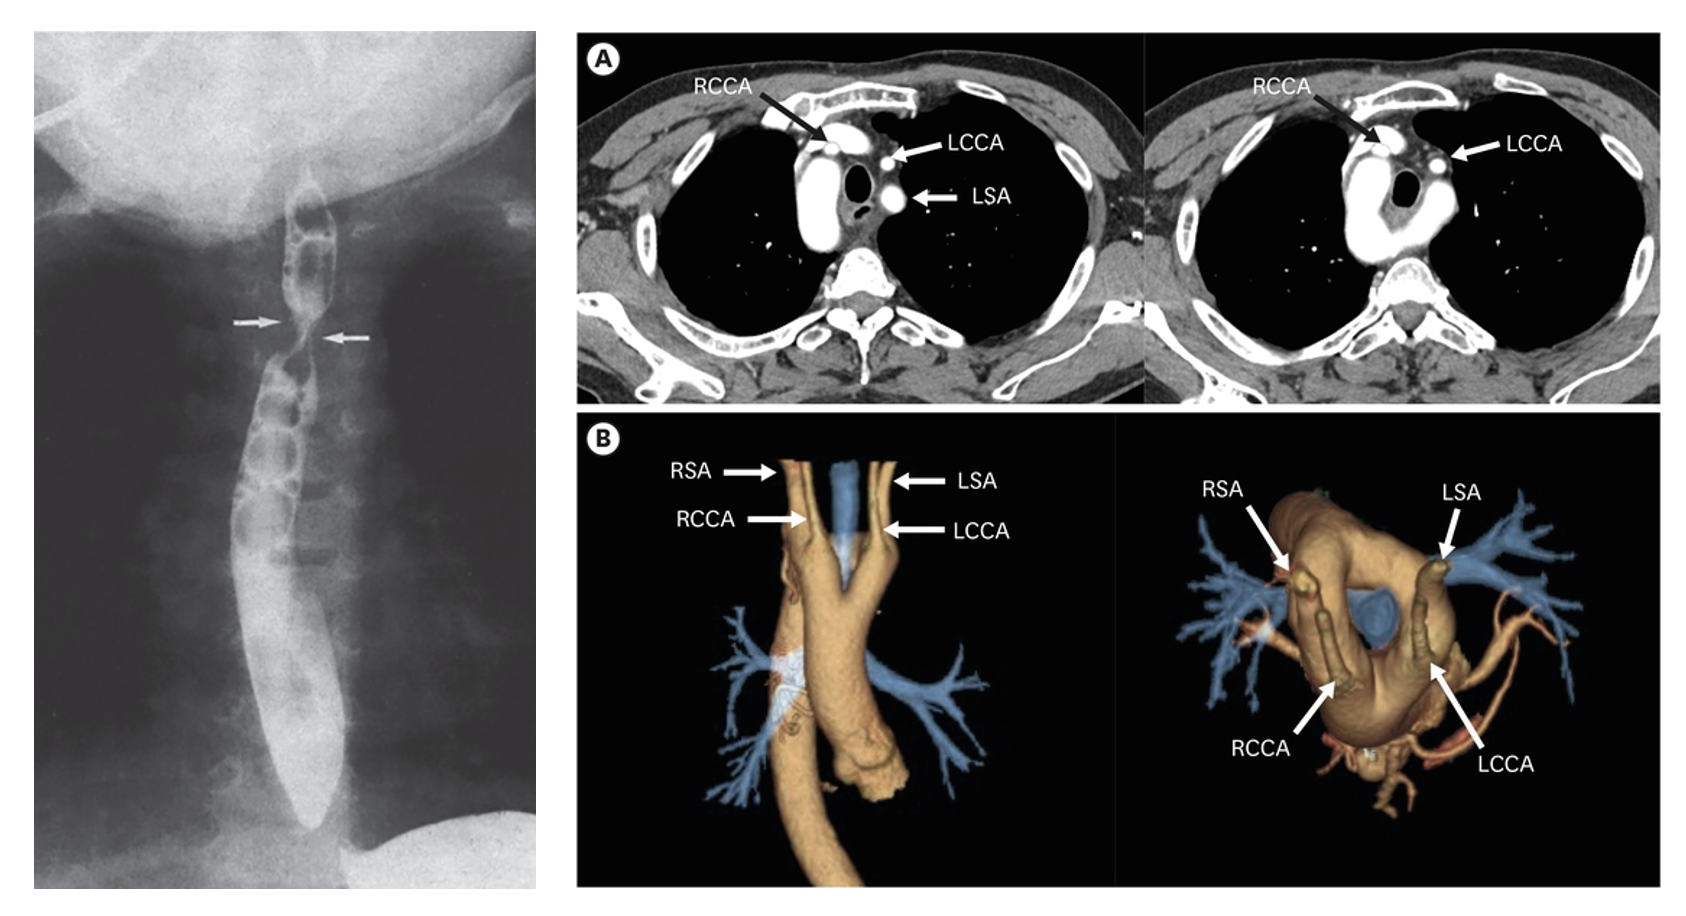

대동맥 활 이상: 좌우 대칭의 고리형태로 이루어진 대동맥 활의 기형

혈관고리: 대동맥활 이상에 의해 기관이나 식도가 혈관 가운데 끼게 되어 호흡장애, 연하장애를 일으키는 질환

진단: 바륨 식도 촬영, CT/MRI